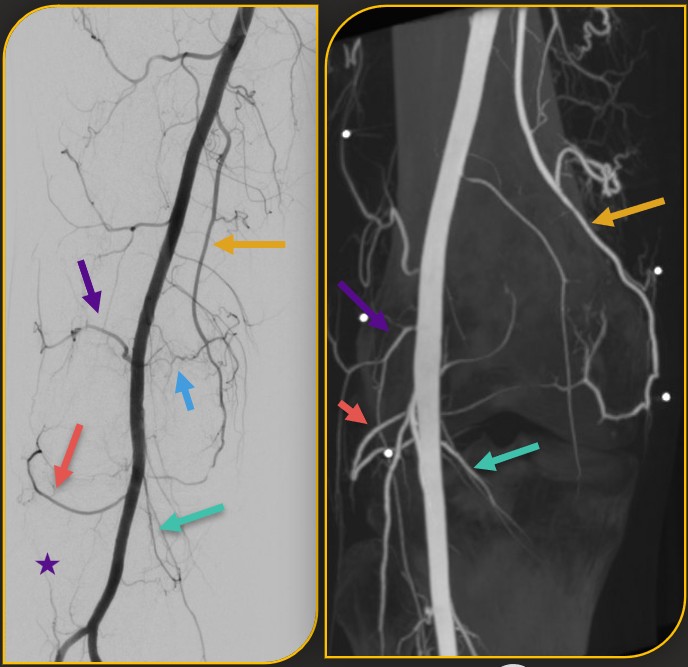

Conventional and cone-beam CT angiography of the superficial femoral artery

Conventional Angiography (left) and Cone-Beam CT Angiography (right) of the superficial femoral artery demonstrate the complex network of genicular arteries surrounding the knee. These images highlight the critical pre-procedural mapping used by interventional radiologists to precisely identify the small, hyperemic vessels targeted during the Genicular Artery Embolization (GAE) procedure for treating knee pain.